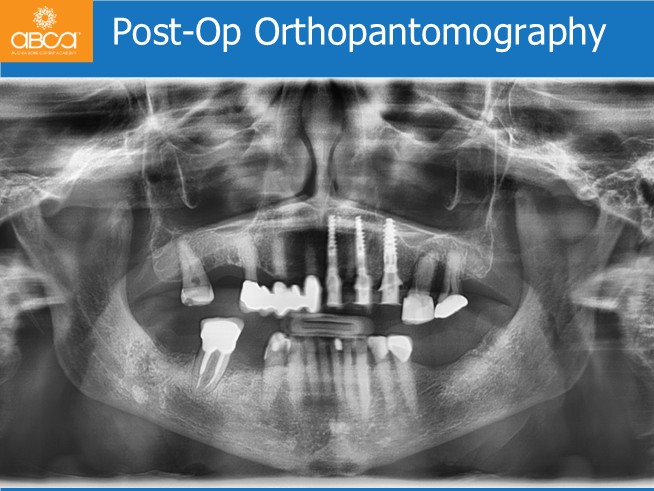

Treatment plan includes extraction of the teeth and roots from #21 (9) to #25 (13). Without opening a flap, placement of 3 immediate implants for an immediate bridge with 5 teeth. Placement of the final Nobel Procera bridge 6 months post-op.